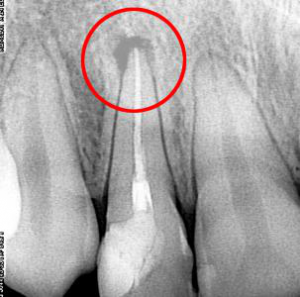

Характерной особенностью данной патологии является то, что развивается она медленно. При незначительных размерах кисты клинические проявления практически отсутствуют. Наличие данного образования диагностируют случайно при рентгенологическом обследовании челюстей, в ходе которого визуализируется овальная структура с четкими краями.

Киста зуба: фото